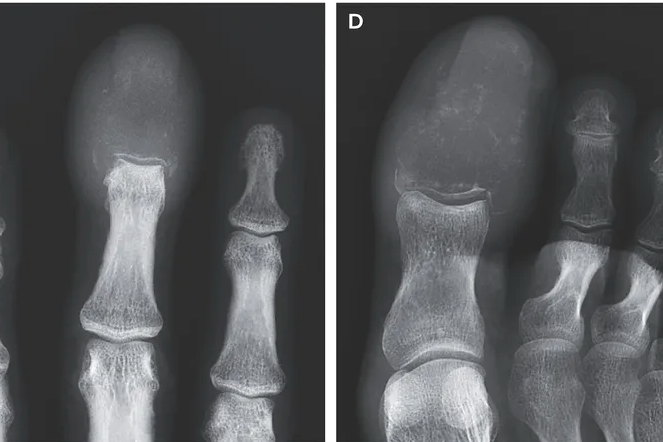

55-летний пациент уже боролся с раком легких, когда у него начали опухать средний палец правой руки и большой палец ноги. Краснота, боль, изъязвление кожи – казалось бы, обычное воспаление. Однако рентген выявил лизис костной ткани: опухоль разрушила фаланги, оставив на их месте пустоты.

Рентген позволяет выявить разрушения костной ткани. В случае пациента, описанного в медицинском журнале, именно снимки позволили установить точный диагноз и начать паллиативную терапию.